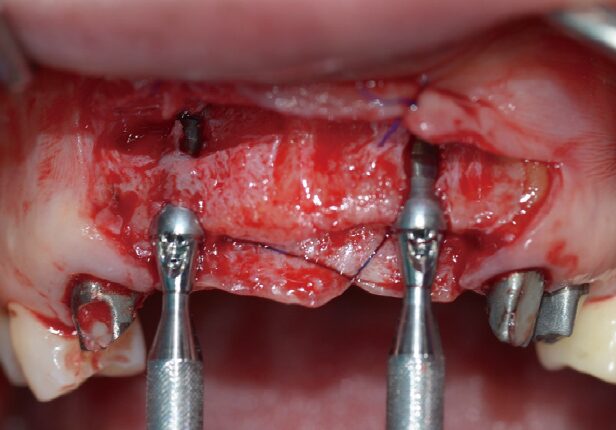

Colocação do implante